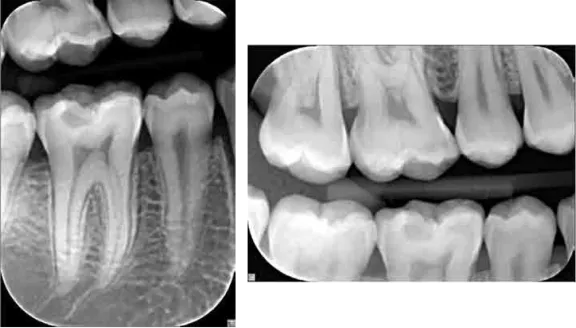

Dokonalost intraorálního rentgenového snímkování.

Rentgenová jednotka FOCUS se díky praktickému designu a inovativní technologii Anti-Drift Mechanism (ADM) vyznačuje stabilitou a spolehlivostí, které odpovídají nárokům moderní stomatologické praxe. Tři různé délky ramen umožňují přizpůsobení jakémukoli uspořádání ordinace, zatímco krátké expoziční časy minimalizují dávku záření pacienta.

Volbou rentgenu FOCUS projevujete péči o své pacienty. Jako vysokofrekvenční intraorální rentgenová jednotka poskytuje FOCUS efektivní expozici, která zaručuje kvalitní snímky při minimální dávce záření. Je také ideální volbou pro digitální snímkování, které vyžaduje krátké a konstantní záření.